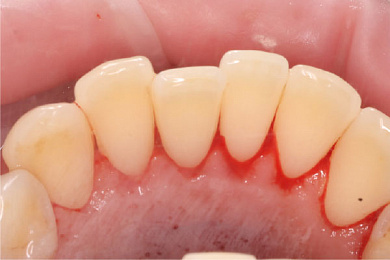

Результат лечения